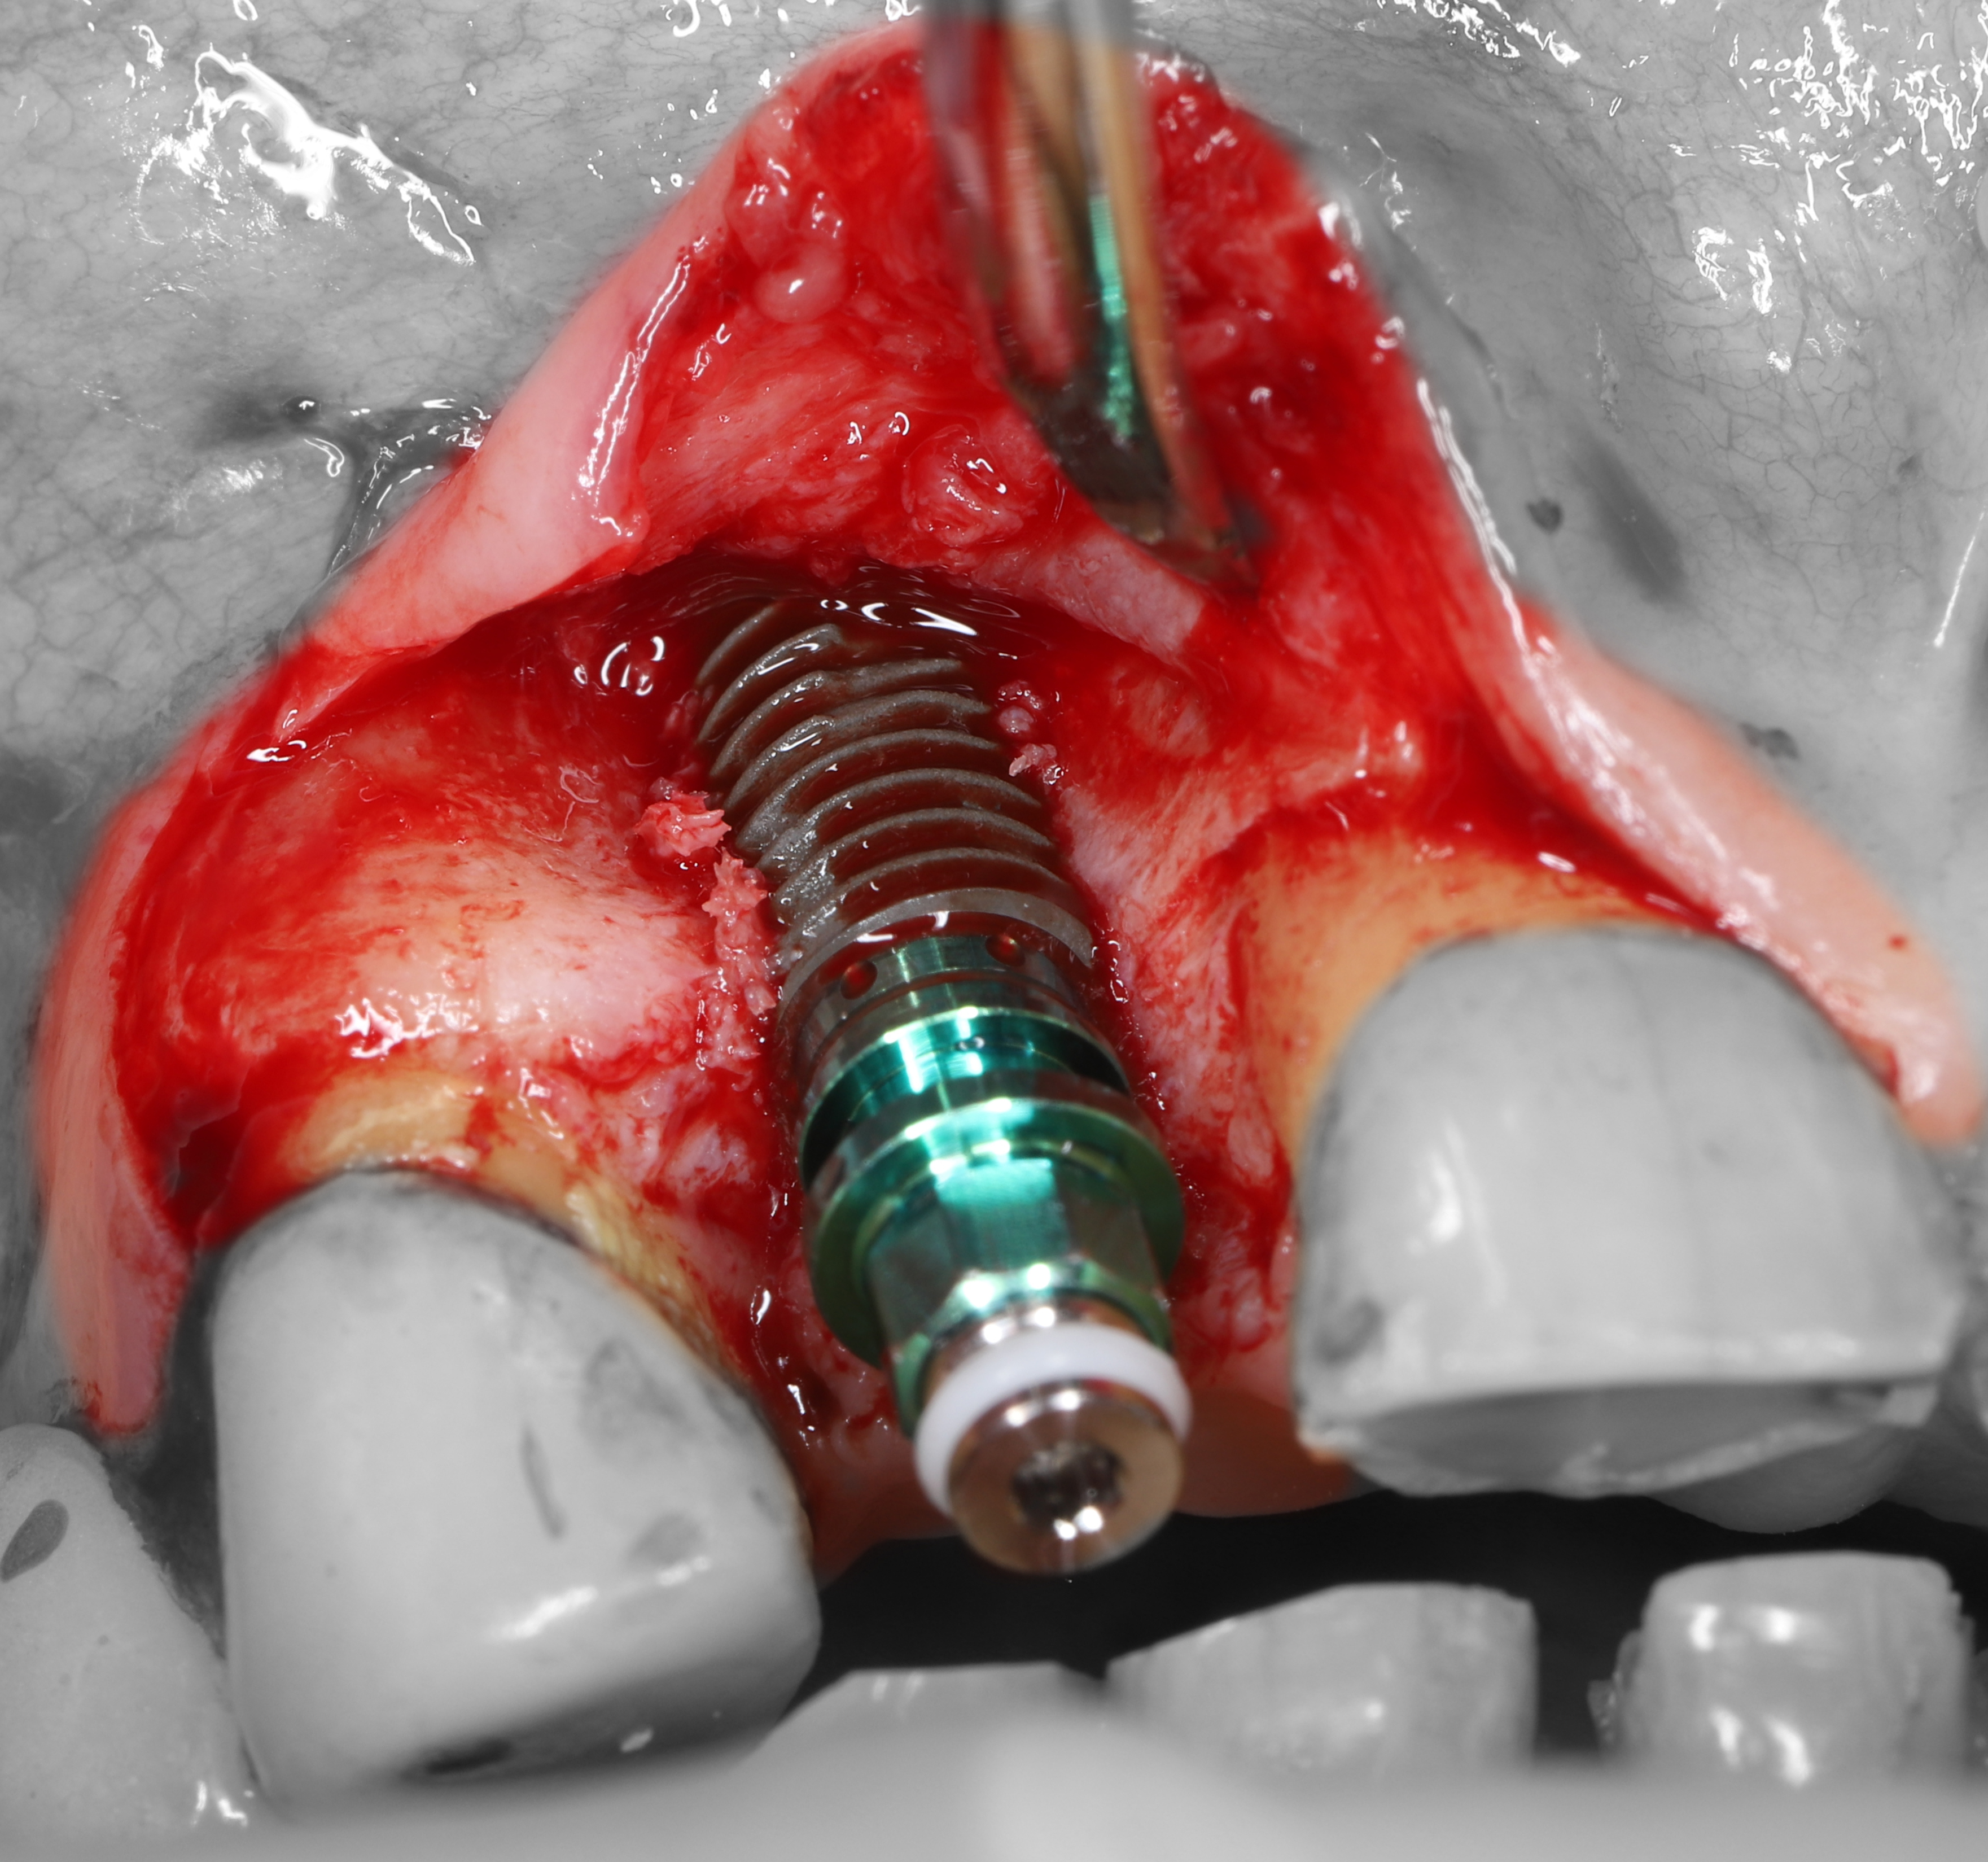

3) Проведена остеотомия имплантантного ложа.

4) Установлен имплантат Osstem 4.5*10 мм., визуализируется выраженная дегистенция имплантата в области вестибулярной костной стенки.